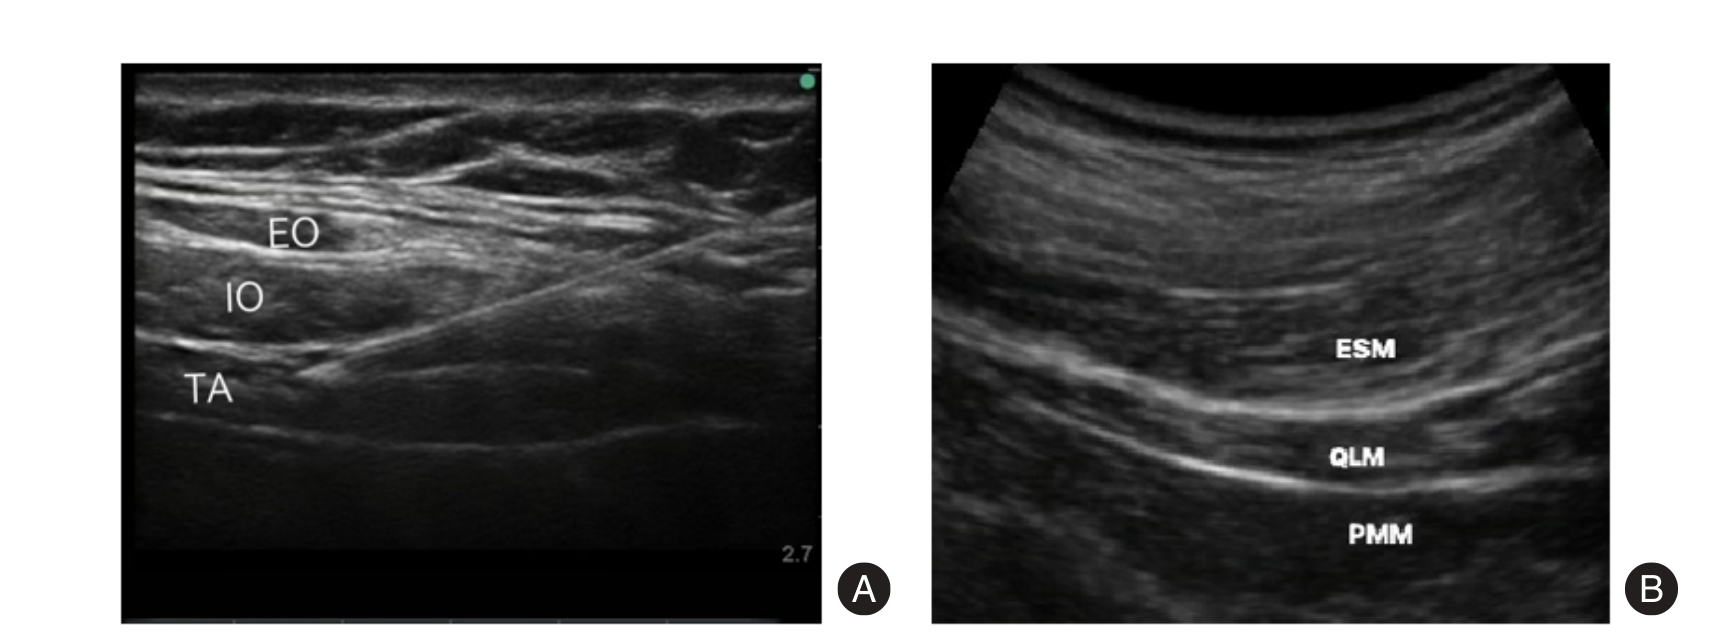

Objective To evaluate the clinical efficacy of ultrasound-guided myofascial trigger point acupuncture in combination with conventional Western medicine for the treatment of primary dysmenorrhea. Methods A total of 112 patients with primary dysmenorrhea who were admitted to the Department of Anesthesiology of Zigong Fourth People’s Hospital from January 2023 to August 2024 were enrolled in the study. These patients were randomly divided into two groups (n = 56 each) by using a random number table. The control group was treated with ibuprofen granules, whereas the observation group received ultrasound-guided myofascial trigger point acupuncture in addition. Therapeutic efficacy, pain intensity, dysmenorrhea symptoms, uterine microcirculation, and serum pain-related mediators were compared between the two groups. Results The total effective rate in the observation group was 94.64%, which was significantly higher than that in the control group (80.36%, P < 0.05). After treatment, both groups experienced reductions in scores on the Short-Form McGill Pain Questionnaire (SF-MPQ), Visual Analog Scale (VAS), resistance index (RI), pulsatility index (PI), systolic/diastolic ratio (S/D), prostaglandin E2, and substance P levels (all P < 0.05). Moreover, the observation group exhibited lower values than the control group in all these aspects (all P < 0.05). Beta-endorphin levels increased in both groups after treatment, and the levels in the observation group were significantly higher (P < 0.05). Conclusion Ultrasound-guided myofascial trigger point acupuncture, when combined with conventional Western medicine, significantly enhances clinical outcomes in primary dysmenorrhea, alleviates pain, improves uterine microcirculation, and regulates serum pain-related mediators.